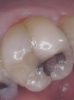

Fig 4. Open-tooth camera photograph confirmed caries exactly where it was displayed on transillumination image.

Figure 4

Figure 1 shows a pretreatment photograph of a tooth No. 20. In Figure 2, the circled area of the x-ray indicates the interproximal area where the clinician was uncertain if caries was present. Though x-rays are useful, transillumination is more sensitive and optimal for detecting caries in the early stages.12 With new devices, clinicians can acquire more information before working on the tooth. As shown in Figure 3, caries was confirmed using the transillumination system (CariVu), though it did not show up on an x-ray. The clinician was able to show the image to the patient. The open-tooth camera image then revealed the extent of the caries in the exact position that was displayed in the transillumination image (Figure 4). This is a significant advantage in minimizing preparations and saving valuable tooth structure.